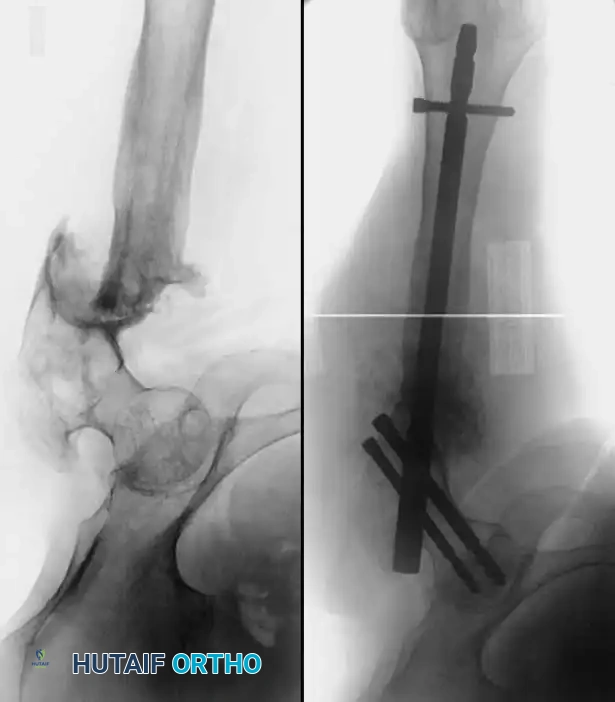

Associated Surgical & Radiographic Imaging